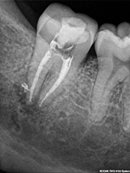

Root Canal Cases